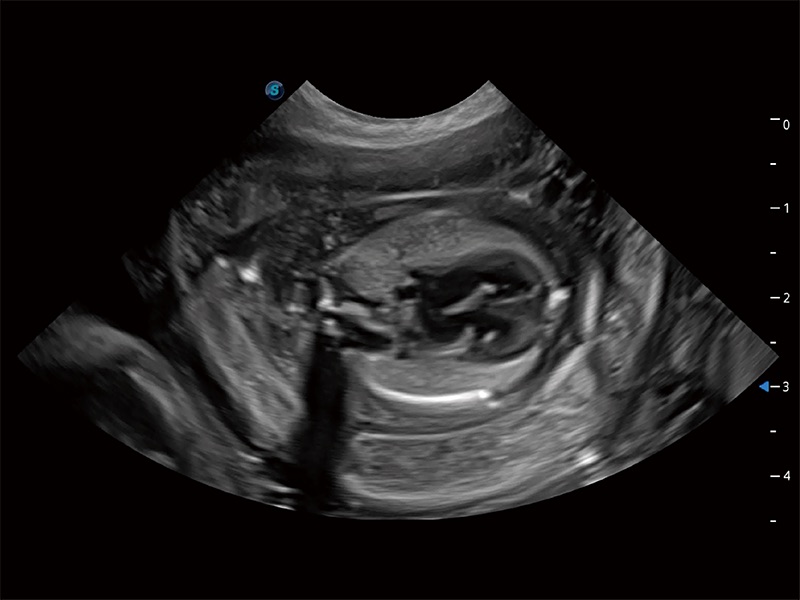

动物是人类最亲密的朋友和最值得信赖的伙伴。乐玩lewin国际也一直致力于探索动物专用的超声影像解决方案。全新推出的ProPet系列,是乐玩lewin国际在动物超声影像智能化、专业化、精准化的一次跨越式革新。动物不能用言语来表述自己的不适,通过超声影像,ProPet系列搭建了动物医生与不同物种沟通的“桥梁”,为动物医生注入了“治愈之力”。 ProPet 80 是乐玩lewin国际匠心打造的一款高端动物专用彩超,采用性能卓越的全新硬件架构,极大提升超声系统的运行效率和数据处理能力,帮助动物医生从容应对日益增多的挑战性病例和日益多样化的临床需求。

高性能和先进的临床应用工具可以为动物医生提供临床信心。ProPet 80 搭载了先进的腹部和浅表应用工具,帮助医生在日常临床实践中发挥前所未有的作用。